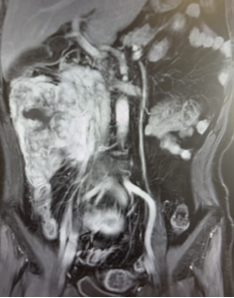

56岁男性患者,因间断上腹不适4个月,检查发现腹膜后肿瘤2周。腹部CT及核磁提示腹膜后巨大脂肪肉瘤,直径约35cm。

我们为患者实施全麻下开放腹膜后肿瘤切除术。术中可见肿瘤挤压十二指肠、胰头、肠系膜血管、下腔静脉和腹主动脉,但未侵犯结肠、肠系膜血管等组织器官,且包膜完整。手术团队仔细游离,完整切除腹膜后肿瘤,剔除腹膜后脂肪。历时2个小时完成,术中出血约100ml。

术后恢复顺利:第3天排气并进食流食;第5天恢复正常饮食;术后第9天出院。术后病理高分化脂肪肉瘤,肿瘤最大径38cm,与肾周脂肪粘连。术后3月随访,未见肿瘤复发。